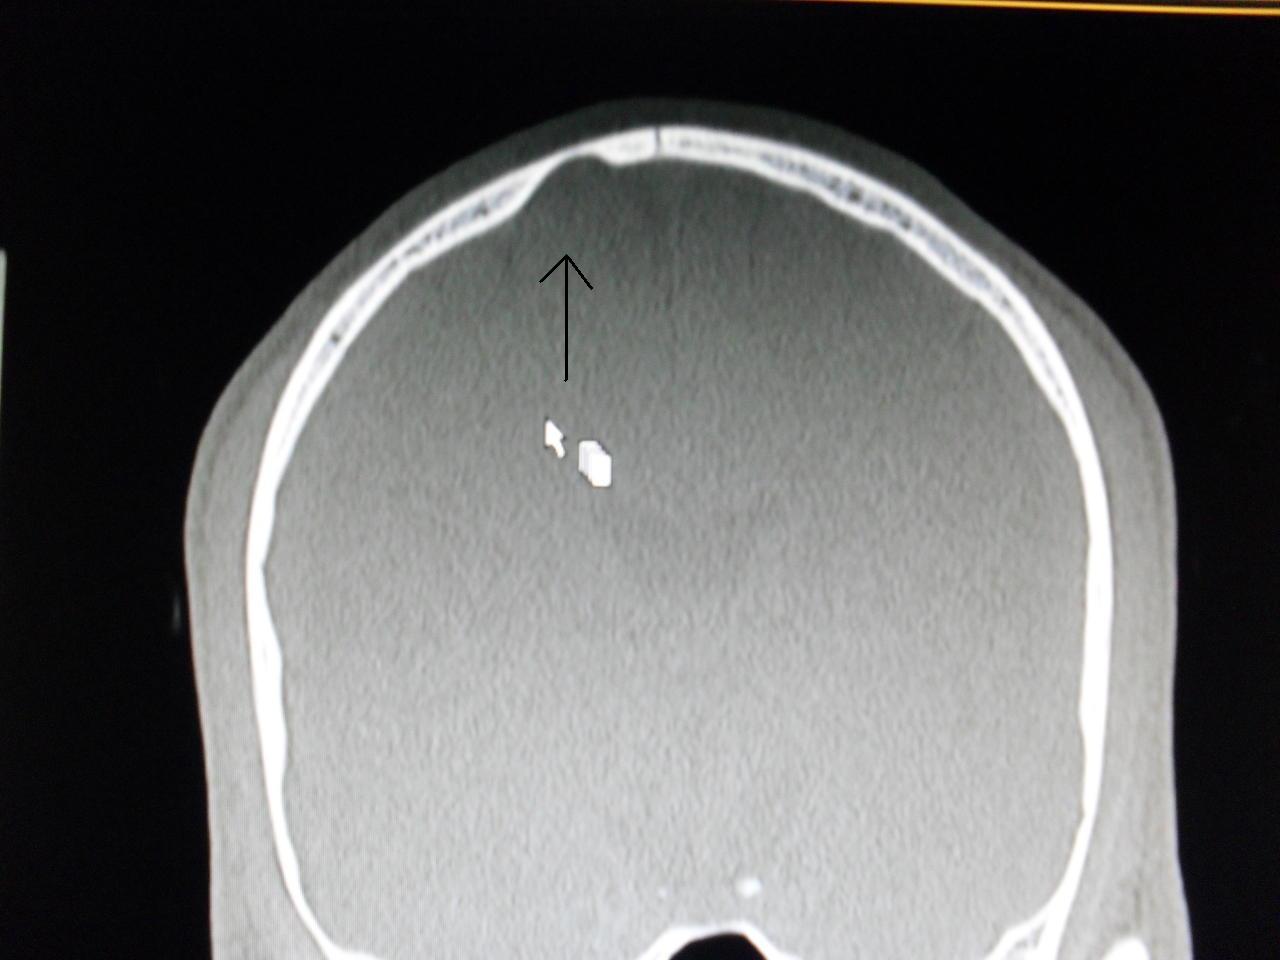

Ein Gehirn ist kein symmetrisches Gebilde, daher sieht es für mich einfach nach einer natürlichen furche oder spalte an der Außenseite in den Windungen aus. Das weiße da drüber ist wohl wieder eine Windung in einer anderen Ebene. Das Bild zeigt nur eine schicht.

Dachte immer, daß man eher auf "weiße Flecken" achten sollte, die einen bösen grund haben könnten.

Soll angeblich ne achadeulalzyste oder sowas sein....nie im leben...naja,ich habe erstmal noch son termien gemacht